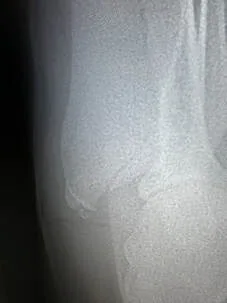

Vi får en hastetime hos K9 Nannestad Dyreklinikk, kjører ned og får tatt bilder av skulderen. Det viser en sprekk i skulderbladet og to små løse beinbiter. Dette er alvor! Slike skader kan gi varige mén og i verste fall ødelegge mulighetene for å få en fungerende jakthund.

Etter et par dager kom tilbakemeldingen: det ser heldigvis ut til ar leddene er uskadd, men sprekken i skulderbladet var jo et brudd og trenger tid. Hun måtte holdes helt i ro i seks uker, da ble det tatt nye røntgenbilder og vi fikk en slags foreløpig fasit på status. Sprekken i skulderbladet hadde delvis grodd, men usikkerheten er først og fremst knyttet til de løse beinbitene.

Dopet ned før røntgenbilder skal tas. Heldigvis er hun i de beste hender hos K9 Nannestad Dyreklinikk.